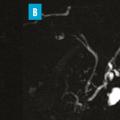

Tumeur kystique mucineuse

Les tumeurs kystiques mucineuses (TKM) sont des lésions précancéreuses bordées par un revêtement épithélial, sécrétant de la mucine. Il est caractéristique de trouver un stroma de type ovarien, positif en immunohistochimie à la progestérone. Le sex-ratio est fortement en faveur des femmes  : (20 femmes pour 1 homme). La découverte est principalement fortuite ou plus rarement sur pancréatite aiguë. Il s’agit d’une lésion unique, macrokystique, sans communication avec les canaux pancréatiques. Elle se situe quasi exclusivement au niveau de la face postérieure du corps et de la queue du pancréas (fig. 3). La lésion est uni- ou multiloculaire, limitée, hypodense, avec rehaussement de la paroi. Il existe de possibles nodules muraux, calcifications périphériques ou cloisons internes.

Le taux de risque d’évolution vers un cancer est inconnu. Les critères comme une taille supérieure à 7 cm, une épaisseur des septas et de la paroi supérieure à 3 mm, un nombre de kystes supérieur à quatre, la présence de nodules, un contenu liquidien hyperintense en séquences IRM T1, une compression ou infiltration périlésionnelle sont associés à des critères de dégénérescence en cystadénocarcinome.11